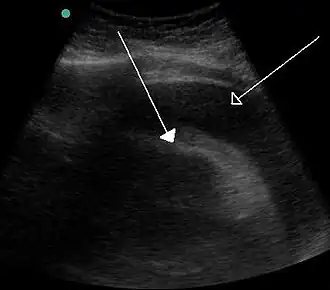

![]() Скопление большого количества жидкости между листками перикарда, видимое при ультразвуковом исследовании. | |

Данное состояние угрожает жизни и без своевременного адекватного лечения может привести к смерти больного. Больной отмечает у себя наличие характерных для сердечной недостаточности жалоб. При разрыве миокарда наблюдается триада Бека, которая включает в себя гипотензию, набухание вен шеи и глухие сердечные тоны. Аускультативно обнаруживаются приглушённые тоны сердца, при ультразвуковом исследовании обнаруживается жидкость между листками перикарда.